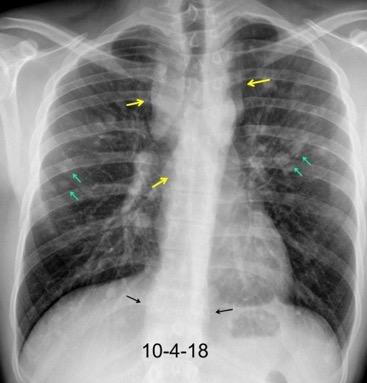

T. mixto de células germinales del testículo izquierdo

Nódulos pulmonares múltiples. (flechas verdes). Masas paratraqueales. (flechas amarillas). Dudoso ensanchamiento retrocrural (flechas negras). sigue….

Ttawfik A et al. Trans-diaphragmatic Pathologies: Anatomical Background and Spread of Disease on cross-sectional Imaging. Current Problems in Diagnostic Radiology. 2021.

T. mixto de células germinales del testículo

izquierdo Metástasis pulmonares. (flechas verdes). Ganglios paratraqueales. (flechas amarillas). Ganglios retroperitoneales (flechas negras)

Tawfik A et al. Trans-diaphragmatic Pathologies: Anatomical Background and Spread of Disease on cross-sectional Imaging. Current Problems in Diagnostic Radiology. 2021.